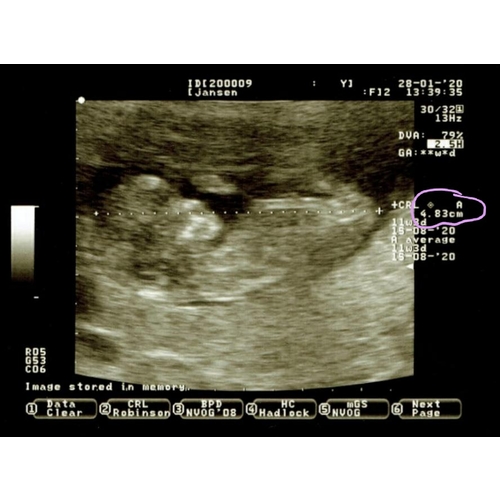

Ja, dit is wel een aparte lengte om mee te krijgen na je termijnecho. Meestal geven ze je de kop-kruin meting (CRL), en pas bij de 20 weken echo een totale lengte.

Hoi! Wat fijn dat je een goede echo hebt gehad! Zoals hierboven al aangegeven, meten ze op dat termijn altijd de CRL (van kruin tot stuit). Op de echo foto van Kitjehekkelman zie je dat ook staan naast het omcirkelde gedeelte. Misschien dat die 11 cm bij jou iets anders betekent? Dit kun je het beste navragen bij je verloskundige 😊

Die 11cm staat volgens mij voor de schermlengte. Dus van links tot rechts op het scherm is 11cm. Lijkt ook te kloppen als de kleine ong. 5cm is, gezien hij de helft van het scherm opneemt. Meen me bij een echo ook te herinneren dat dit getal veranderde wanneer ze verder in- of uitzoomden.